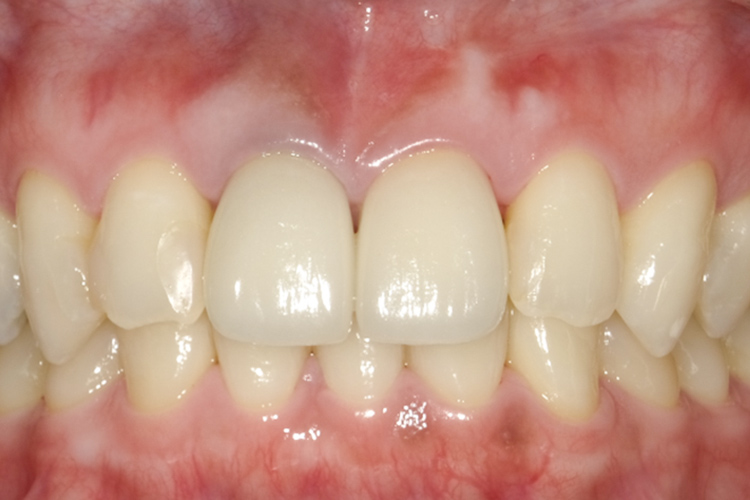

治療前

治療後